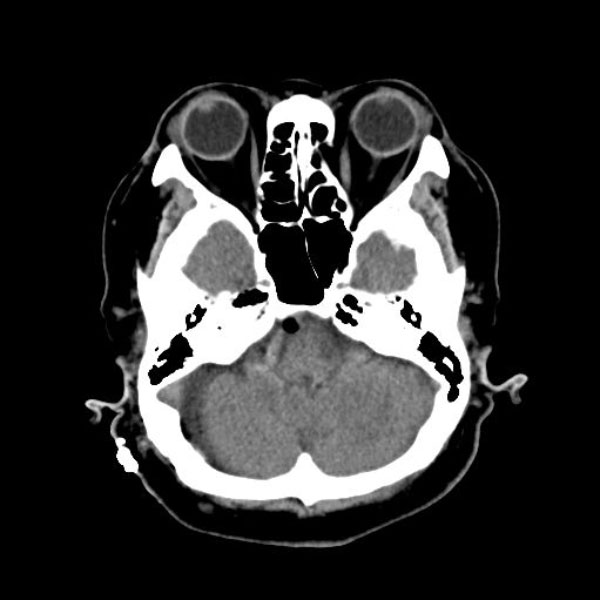

手術後

(CT)